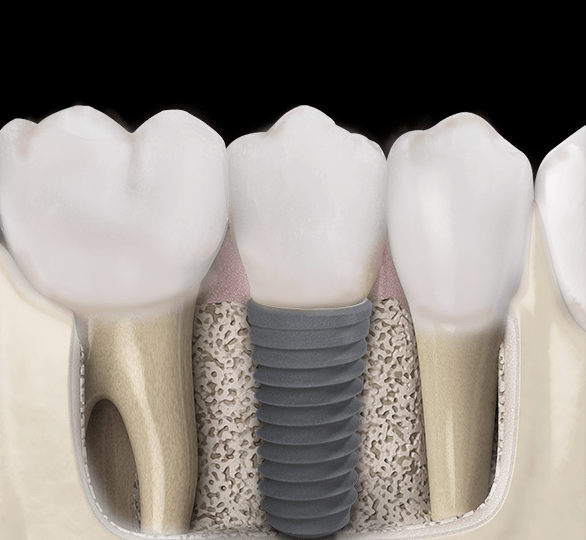

IMPLANTES

Un implante es un dispositivo de titanio que sustituye a la raíz de una pieza dentaria perdida. Se utilizan para rehabilitar una pieza de manera individual, varias piezas, o todo un maxilar edéntulo.

El titanio es un metal altamente biocompatible, con alta estabilidad química y buenas propiedades mecánicas.

Cuando la pérdida de piezas dentarias es parcial, se sustituyen con coronas o puentes implanto asistidos.